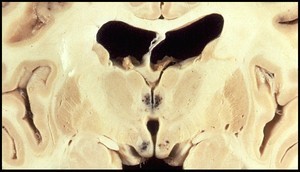

A 65 year old homeless man is brought to the emergency room for severe alcohol intoxication. He is given IV fluids and glucose for ressucitation and he appears to improve. On exam the next day however, he has developed some palsy of the lateral rectus muscles and has an inward gaze (esotropia). While interviewing the patient, the physician asks him what year it is, to which the patient replies, “1975”. Out of curiousity, the physician then asks him what color the dog standing next to him is. The patient confidently replies, “that’s a beautiful golden retriever”. Based on the symptoms and gross specimen below, what has happened?

Wernicke’s Encephalopathy:

Petechial hemorrhages present in the mamillary bodies and walls of the third ventricle. (infarction of mamillary bodies)

- Due to thiamine deficiency.